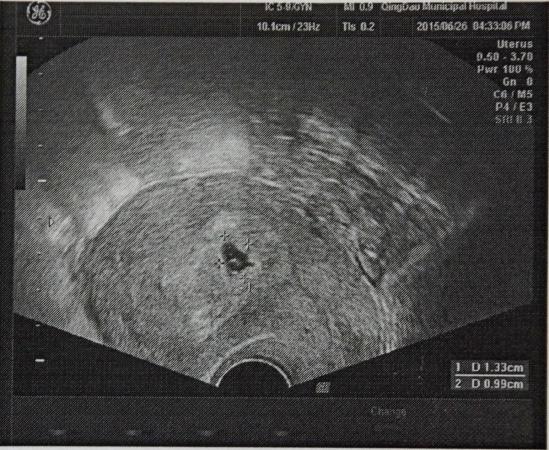

感谢各位的热心回答,今天去医院又做了检查,新拍了一张B超,我感觉形状还不是那种规则的圆形或椭圆形。还得麻烦各位给看一下,形状是否正常呢?现在有了胎心和胚芽,但还是有出血现象。